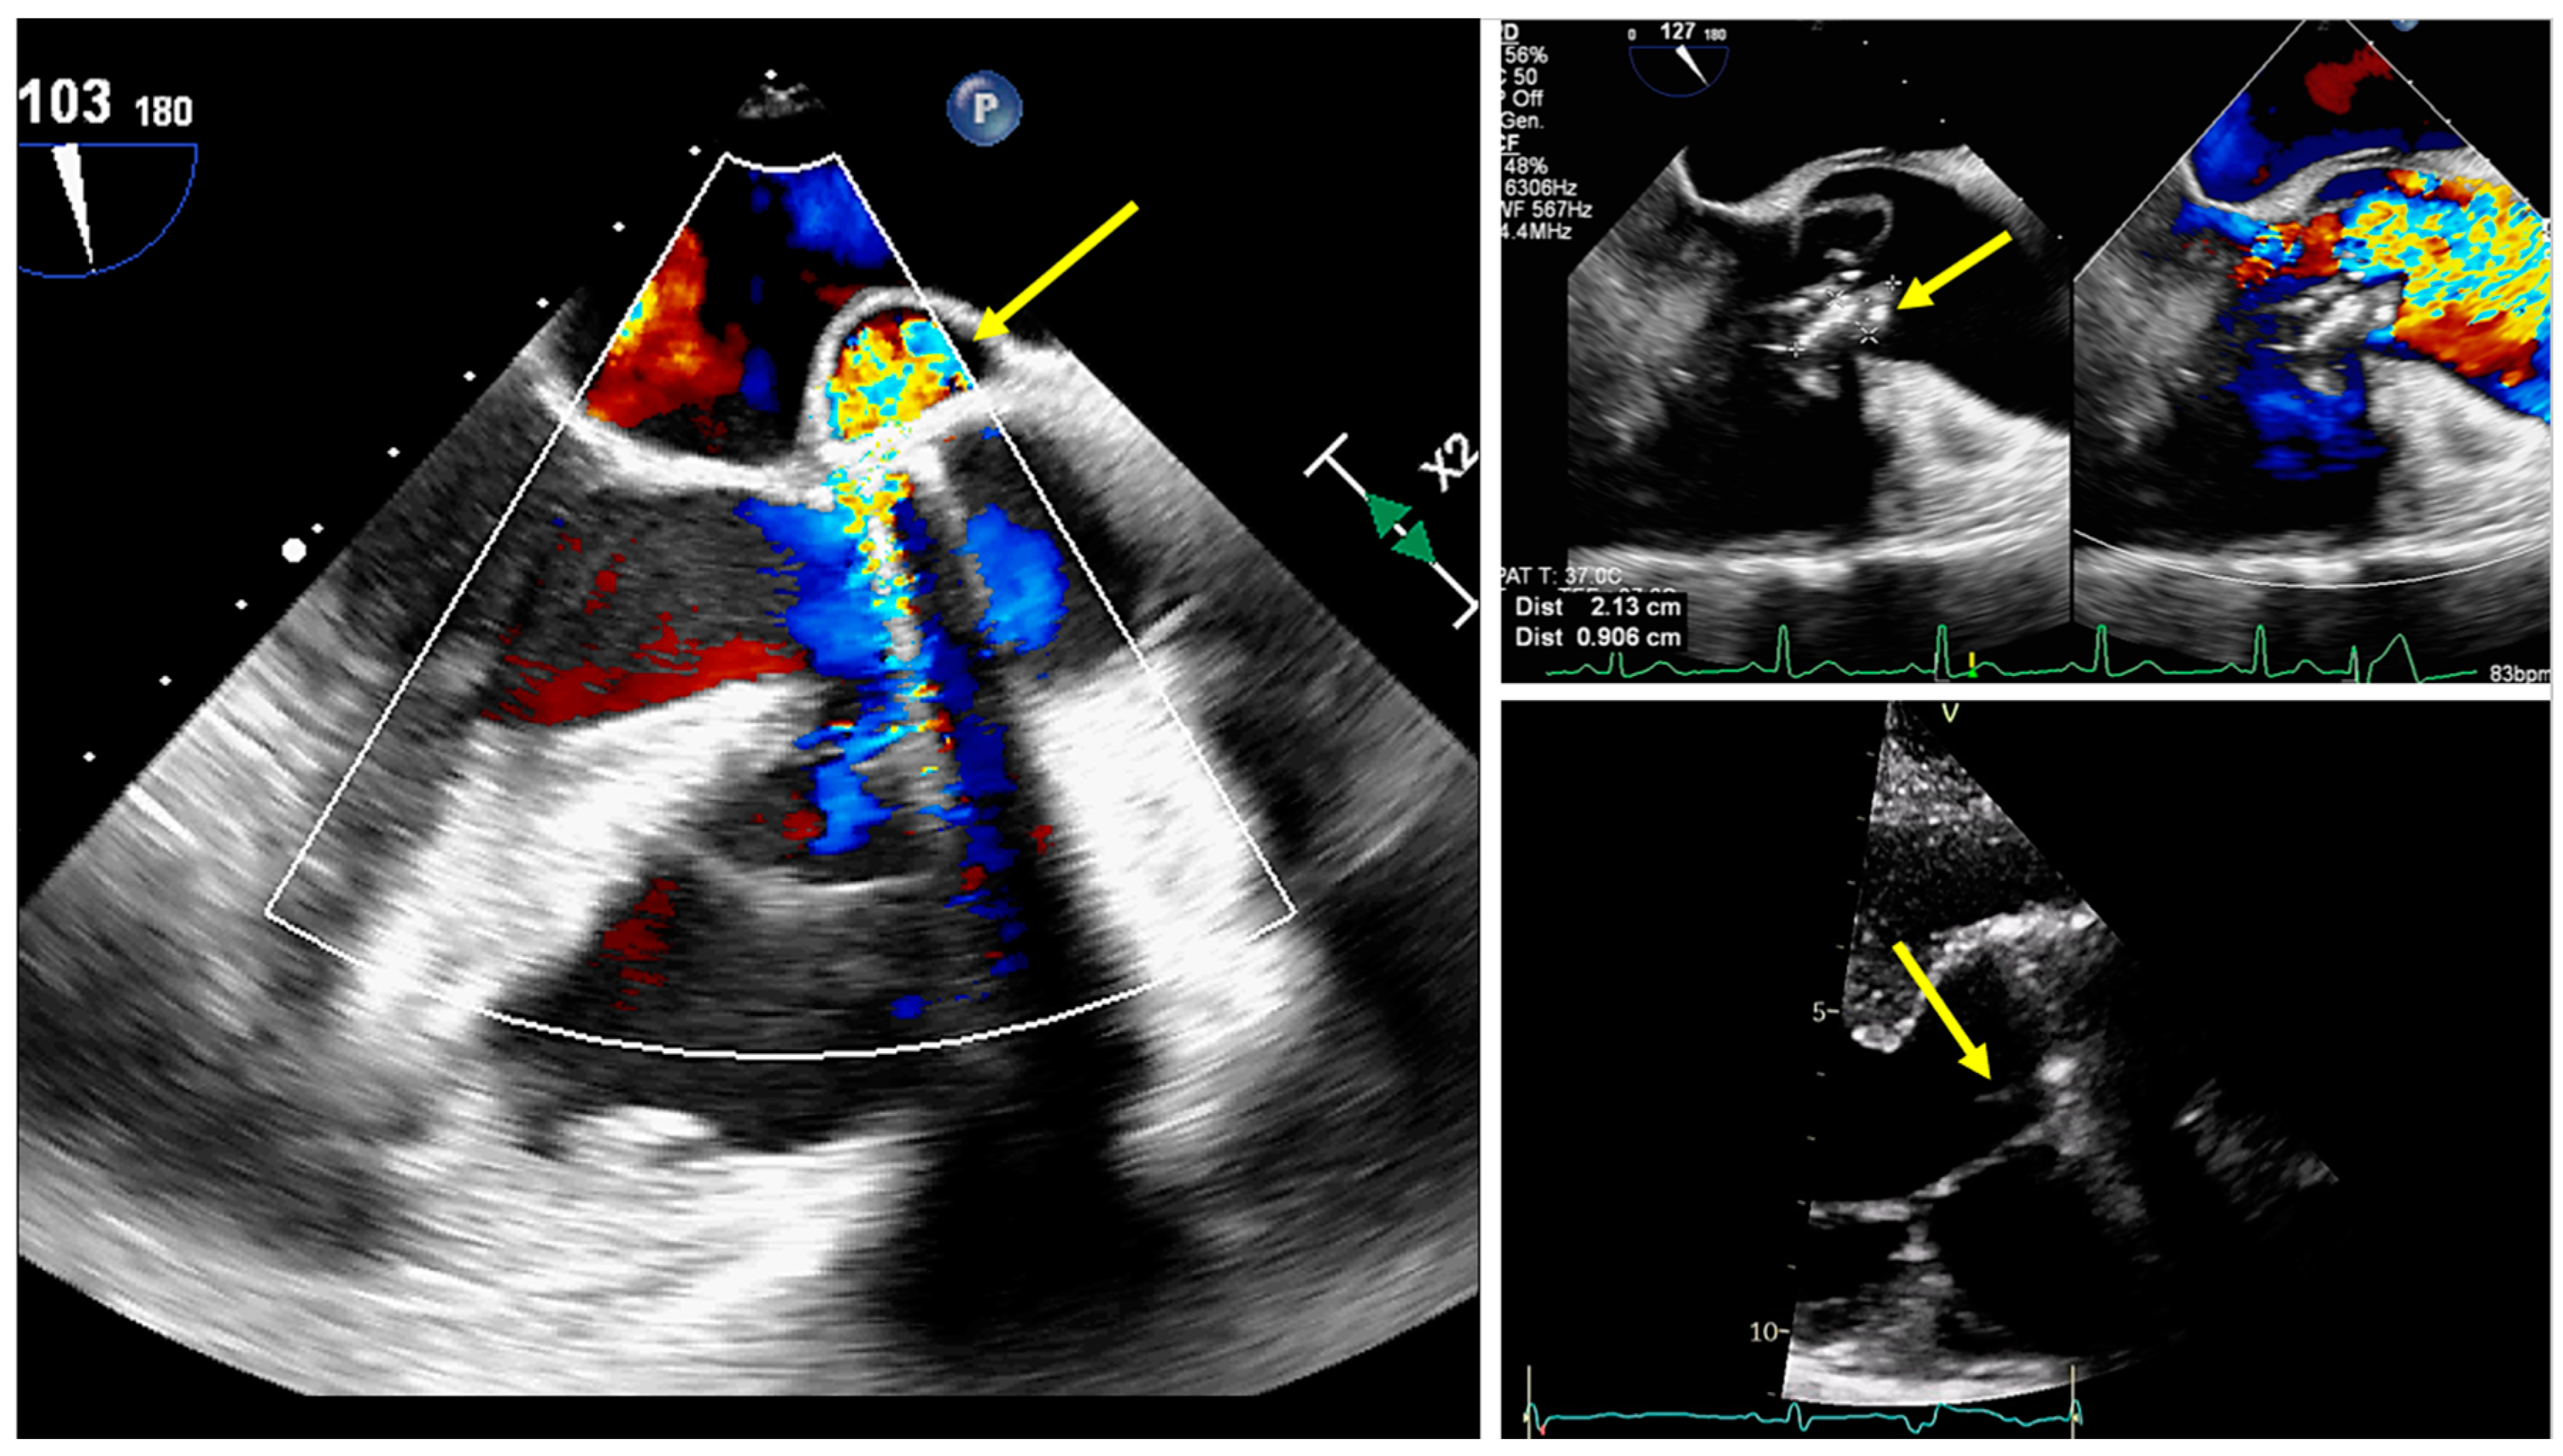

3.2. Role of Echocardiography

- Fusco, F.; Scognamiglio, G.; Correra, A.; Merola, A.; Colonna, D.; Palma, M.; Romeo, E.; Sarubbi, B. Pulmonary valve endocarditis in adults with congenital heart disease: The role of echocardiography in a case series. Eur. Heart J. Case Rep. 2020, 4, 1–7. [Google Scholar] [CrossRef]